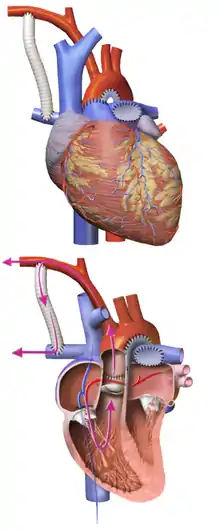

Norwood procedure

The first step is the Norwood procedure.[32] In this procedure, the right ventricle is used to pump blood into the systemic circulation. Since the right ventricle is no longer directly pumping blood to the lungs, a shunt is required in order to pass deoxygenated blood through the lungs. Either the subclavian artery can be connected to the pulmonary circulation (Blalock-Taussig shunt), or a shunt is made directly from the right ventricle to the pulmonary circulation (Sano shunt). The narrow aorta is enlarged using a patch to improve blood flow to the body.[33]

During this time the baby may be medically fragile and have feeding problems because the heart is working very hard. There is a considerable degree of venous mixing in the right ventricle, leading to lower oxygenation saturation. In addition, both the Blalock-Taussig and the Sano shunts expose the lungs to systemic arterial pressures, leading to long-term pulmonary hypertension and eventually heart failure.[32]

Hybrid procedure

The Hybrid procedure may be used in place of the Norwood.[32][34][35] The Hybrid procedure does not necessitate the use of heart-lung bypass or performing a sternotomy. Instead of a six-hour surgery, the Hybrid typically takes one to two hours. In this procedure, a stent is placed in the ductus arteriosus to maintain its patency, and bands are placed over both the left and right pulmonary artery branches to limit pressure and over-circulation to the lungs.[36] Outcomes with the Hybrid approach are comparable to those with the Norwood.[37]

Glenn procedure

The second stage—the bidirectional Glenn or Hemi-Fontan (see also Kawashima procedure)—relieves some of the problems introduced by Stage I palliation.[32] In this operation, the superior vena cava is ligated from the heart and connected to the pulmonary circulation. At this time, the Blalock-Taussig or Sano shunt is taken down. The lungs are no longer exposed to systemic arterial pressures, but much lower venous pressures. Although venous blood from the upper half of the body is no longer mixing with oxygenated blood in the right ventricle, there is still venous mixing from the lower half of the body, leading to some degree of oxygen desaturation.[32]

Fontan procedure

The final procedure, the Fontan procedure, completes the repair of the hypoplastic left heart.[32] Although there are several variations, the functional effect is to redirect venous blood from the lower body (through the inferior vena cava) away from the right atrium to the pulmonary artery. This should eliminate any mixing of oxygenated and deoxygenated blood in the right ventricle. The right ventricle performs the traditional job of the left, supplying the body with oxygenated blood, while the passive systemic venous pressure performs the traditional job of the right, passing deoxygenated blood to the lungs.[32]